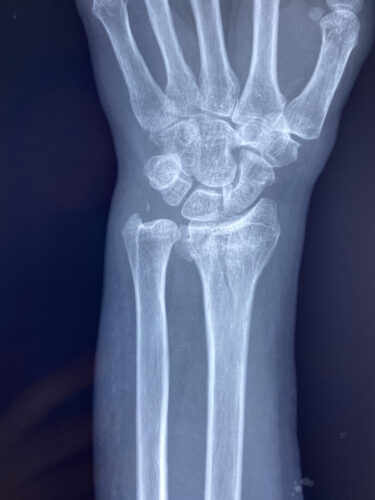

さわやか千葉県民プラザ(前腕骨下端部骨折)